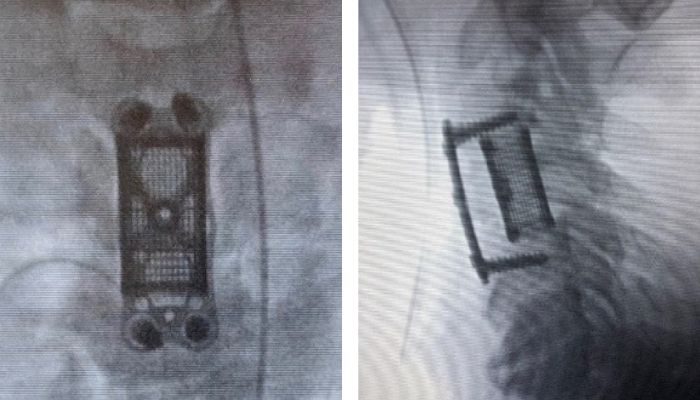

Des implants en titane imprimés en 3D

La société américaine Nexxt Spine est spécialisée depuis plusieurs années dans la production d’implants pour les troubles de la colonne vertébrale. Avec Nexxt Matrixx, l’entreprise a réussi une autre innovation : les implants en titane imprimés en 3D sont censés favoriser l’ostéogenèse, améliorer la topographie de surface et la production de facteurs angiogéniques. L’entreprise utilise les équipements de GE Additive pour la fabrication de ses implants et s’appuie sur le procédé DMLM pour produire ses composants en titane. Andy Elsbury, fondateur de Nexxt Spine, affirme que les patients ainsi que les cliniques bénéficient grandement de la résistance et de la biocompatibilité des implants en titane.